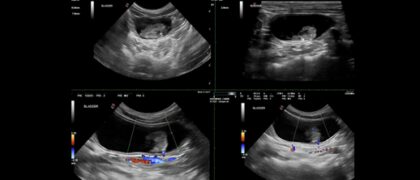

In diesem vetinar widmen wir uns den sonographischen Veränderungen der Harnblase bei Hund und Katze. Besprochen werden typische und atypische Befunde wie Wandverdickungen, intraluminale Strukturen, Harnblasensteine, Neoplasien und entzündliche Veränderungen. Anhand praxisrelevanter Beispiele werden sonographische Merkmale, Differenzialdiagnosen sowie Fallstricke der Interpretation erläutert.